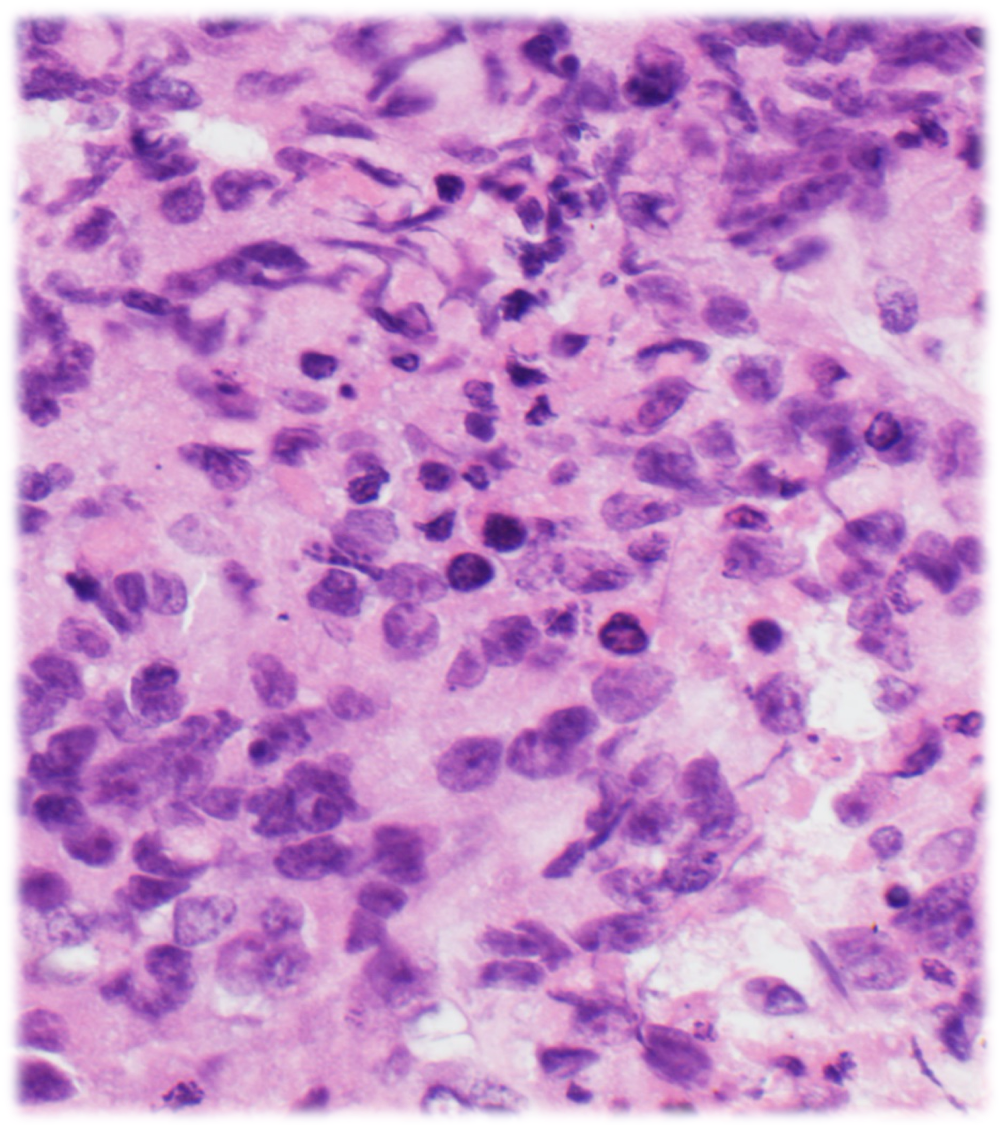

The specimen is highly cellular and consists of medium to large-sized atypical cells with moderate amounts of basophilic cytoplasm, prominent nucleoli and macronucleoli, some binucleation and multinucleation, and some plasmacytoid and rhabdoid morphology, present singly in a background of lymphocytes. Necrosis and mitotic figures are readily identified.

Morphologically, the cases can have sarcomatoid (undifferentiated round cells/rhabdoid) appearance, and can also have areas of conventional non-small cell carcinoma. Hallmarks of round cell morphology are discohesive round to oval cells with prominent nucleoli and overall monomorphism despite being overtly high grade; rhabdoid cells with distinctive hyaline cytoplasmic inclusions can be admixed.